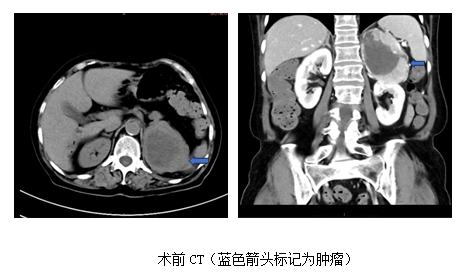

心内科后,赵永勇医师高度重视,予以高血压病因筛查,CT发现左肾上腺区8cm占位,考虑嗜铬细胞瘤可能,肿瘤密度不均匀,显著不均匀强化。同时,查24小时尿儿茶酚胺,显示多巴胺,去甲肾上腺素,甲氧基去甲肾上腺素3甲氧酪胺及香草扁桃酸升高数倍,目前西北区域仅五楼自拍